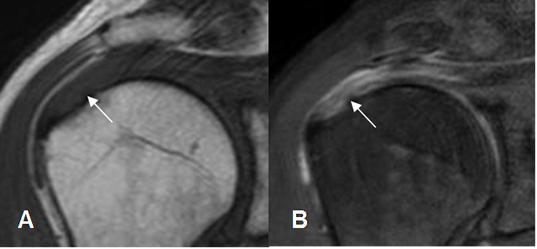

Fig 132. Tendinitis aguda del supraespinoso.

A: RM coronal en T1 y B: RM coronal en STIR. Tendón del supraespinoso hiperintenso y rodeado por líquido, por inflamación aguda.